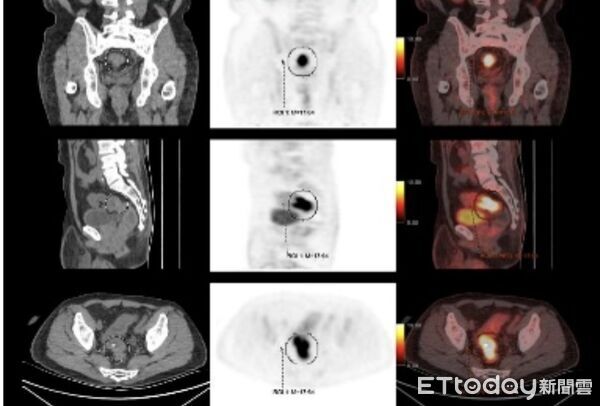

▲43歲男消化不良就醫,竟罹「直腸癌第3期」嚇壞。(圖/記者賴文萱翻攝)

43歲趙先生左腹疼痛和腹脹一個多月,雖然大便習慣改變,但無便秘或腹瀉,無血便也無家族病史,他以為只是一般的消化不良,沒想到就醫檢查後竟在直腸發現有1顆5公分腫瘤,後續確診直腸癌第3期,所幸術後接受化學治療,降低復發風險,後續持續追蹤。

蔡達基指出,趙先生接受結合3D影像系統與4K高畫質放大螢幕的經肛門微創腹腔鏡手術,順利將直腸病灶腫瘤切除,雖然腫瘤沒有侵犯肛門括約肌,但考慮腸道縫合處滲漏的風險,仍為趙先生做暫時性腸造口(人工肛門),以便袋收集排泄物,等3個月後吻合處傷口完全癒合,再將腸造口關閉,就能正常排便。